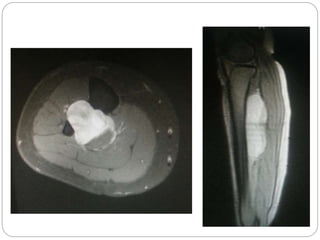

This document discusses 8 oncology cases. Case 1 involves a 40-year old female with right knee pain. Case 2 is a 28-year old male with a left subtrochantric fracture from a MVA who is now experiencing increasing left knee pain and swelling. Biopsy results showed high-grade osteosarcoma. Case 3 is a 30-year old female with breast cancer and bone metastases causing bilateral hip pain.